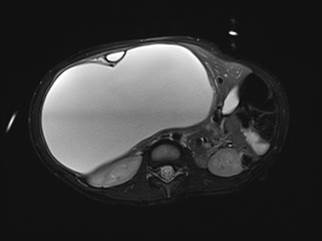

An abdominal x-ray was performed, which showed striking hepatomegaly. Ultrasound demonstrated a multicystic mass (17.7 x 16.3 x 12.6 cm) in the right upper quadrant with thick septations and internal debris. MRI revealed mass effect on the adjacent structures, including upward displacement of the right hemidiaphragm and compression of the right kidney (Figures 1 and 2).